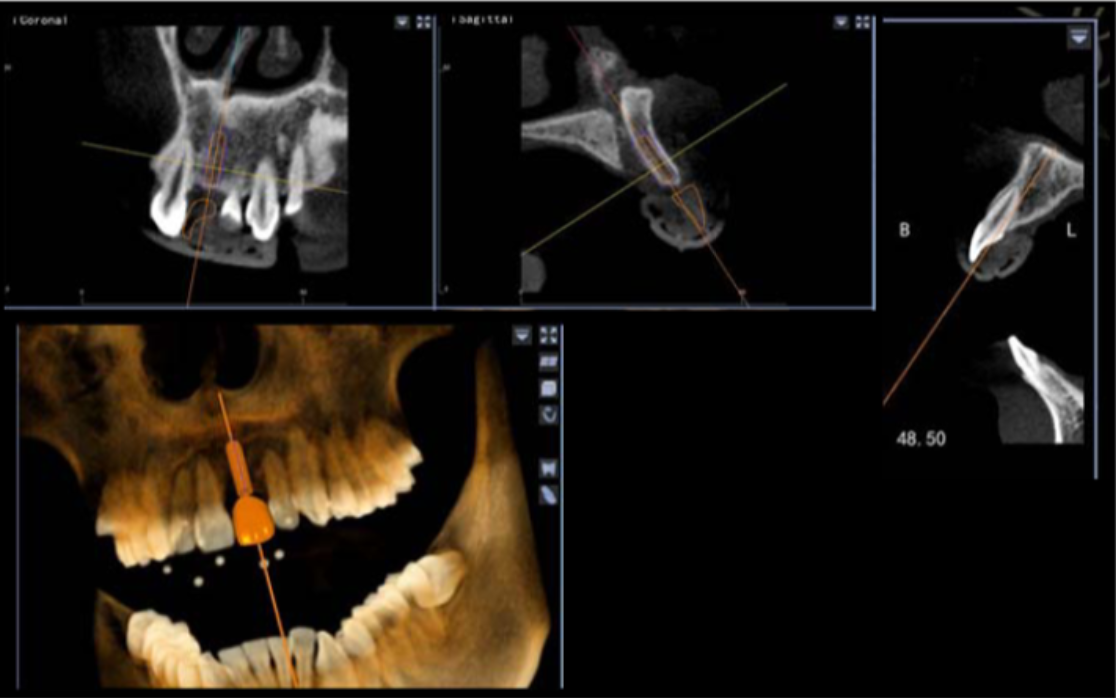

避免骨劈開及切牙管,這是由華西口腔的楊醒眉教授主刀的一次完美的前牙美學(xué)區(qū)數(shù)字化種植手術(shù)的病例!